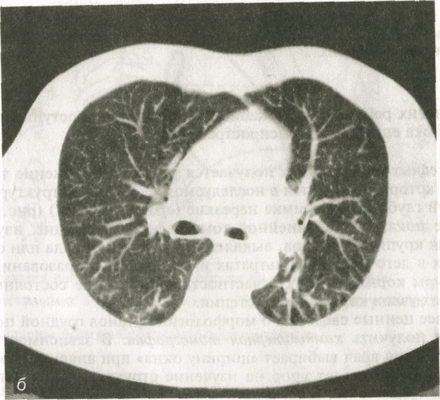

Более ценные сведения о морфологии органов грудной полости позволяет получить компьютерная томография. В зависимости от цели исследования врач выбирает «ширину окна» при анализе изображения. Тем самым он делает упор на изучение структуры либо легких, либо органов средостения.

В нормальных условиях плотность легочной ткани, по данным денсито-метрии, колеблется от —650 до -850 Н. Такая низкая плотность объясняется тем, что 92 % легочной паренхимы составляет воздух и лишь 8 % — мягкие ткани и кровь в капиллярах. На компьютерных томограммах определяются тени легочных артерий и вен, четко дифференцируются главные, долевые и сегментарные бронхи, а также межсегментарные и междолевые перегородки.

Рис. 5. Компьютерные томограммы легких одного и того же пациента, выполненные при разных технических условиях.

а - для исследования органов средостения; б - для исследования легочной ткани.

Фоном для медиастинальных органов является жировая клетчатка средостения. Ее плотность колеблется от -70 до —120 HU. В ней могут быть заметны лимфатические узлы. В норме они круглой, овальной или треугольной формы. Если величина узла превышает 1 см, то его считают патологически измененным. С помощью срезов на разной глубине получают отображение пре- и паратрахеальных лимфатических узлов, узлов в аортопульмональном «окне», в корнях легких и под бифуркацией трахеи. КТ играет важную роль в оценке состояния органов средостения: она позволяет изучить тонкие детали морфологии легочной ткани (оценка состояния долек и перидольковой ткани, выявление бронхоэктазий, участков бронхиолярной эмфиземы, мелких очагов воспаления и опухолевых узелков). КТ часто необходима для установления отношения обнаруженного в легком образования к пристеночной плевре, перикарду, ребрам, крупным кровеносным сосудам.